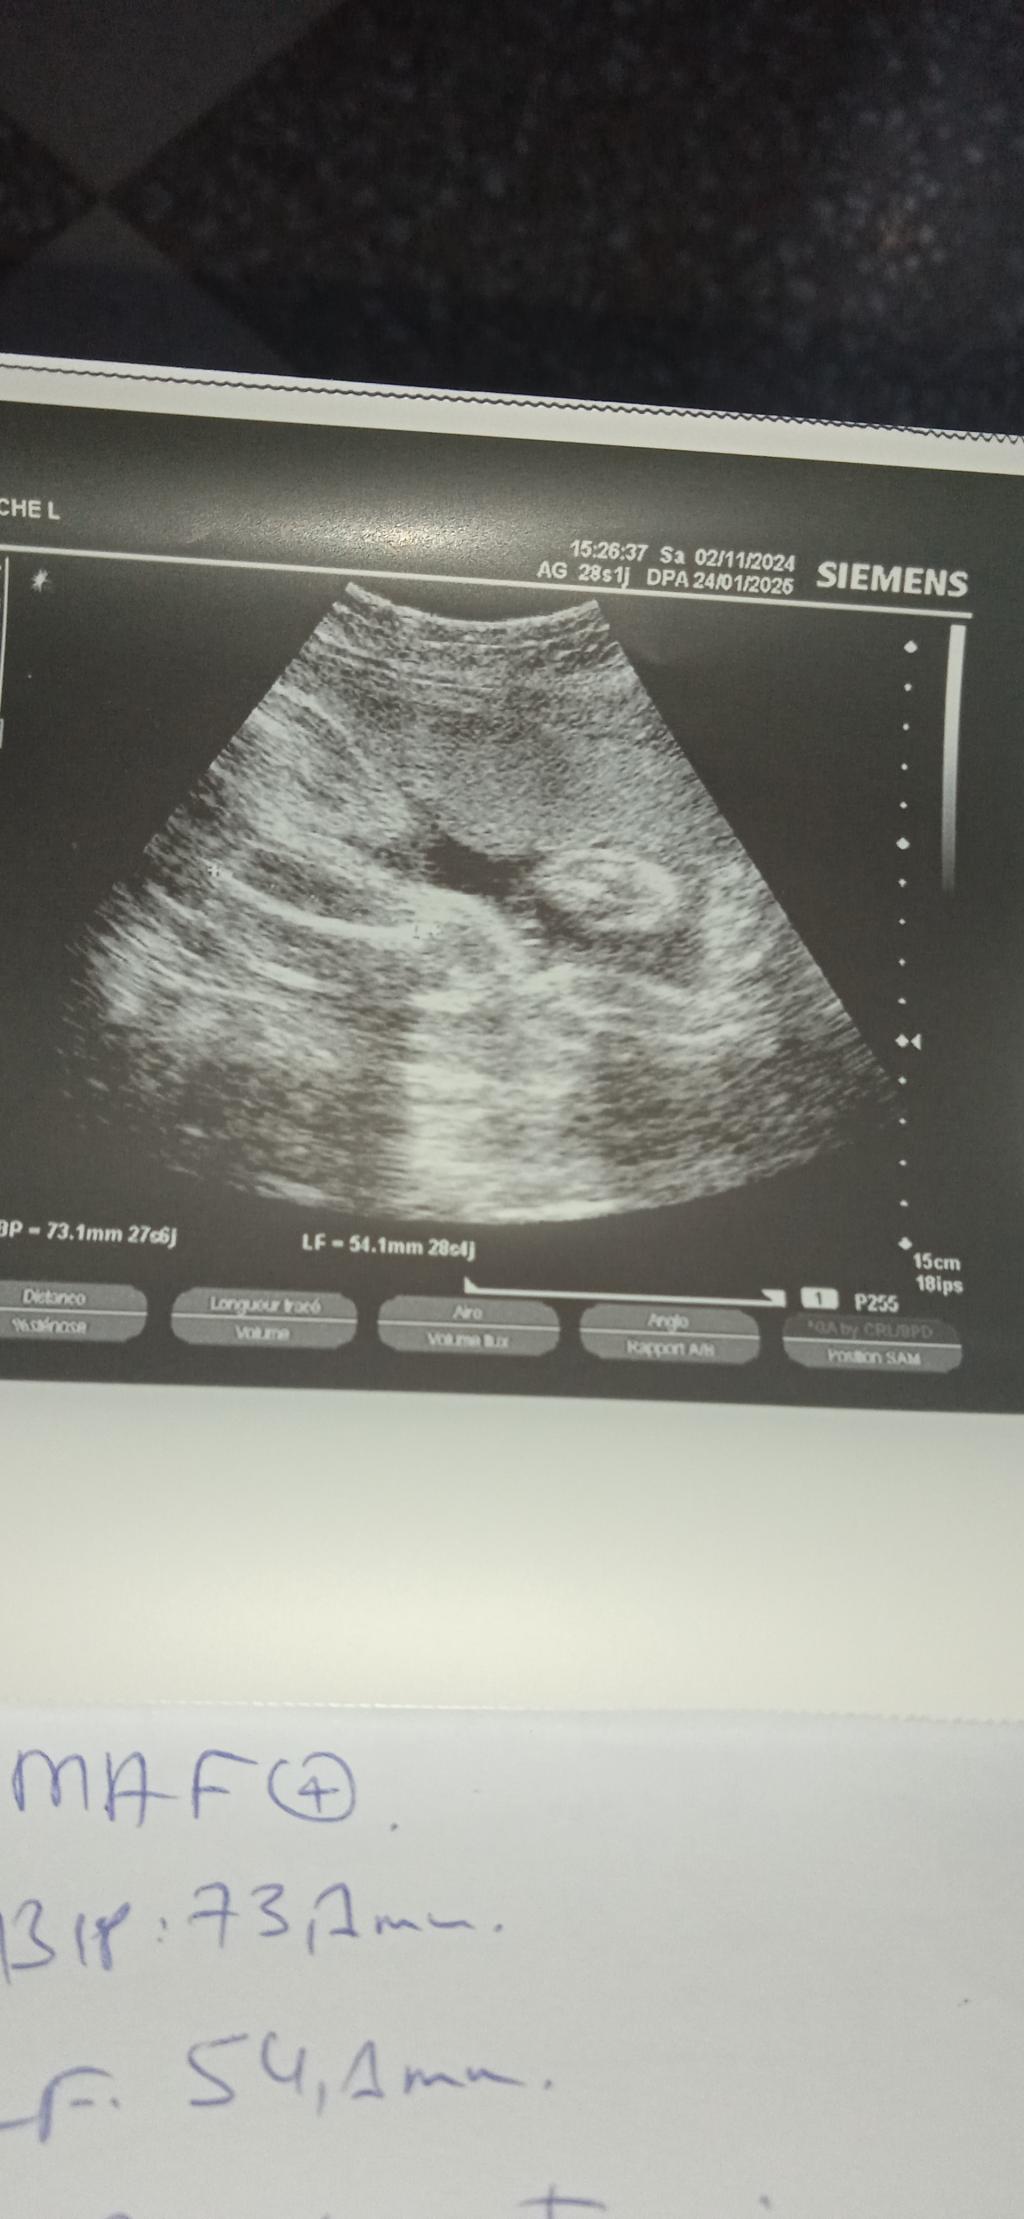

سونار جنس الجنين

بنات هذا سوناري في الشهر الرابع وقالت تعالي نهاية الخامس نتأكد ، قالت ٦٠٪؜ بنت

انتو شو شايفين

مافيه صورة ظاهرة .

وليش نهاية الخامس ترى الحين يبين واضح و لو تروحين لوحدة فاهمه بالسونار بتعرف على طول اذا جلسته زينه